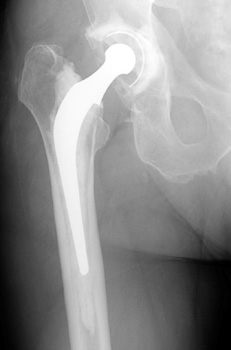

• Non cemented

• Porous coated

• Press fit

Non Cemented